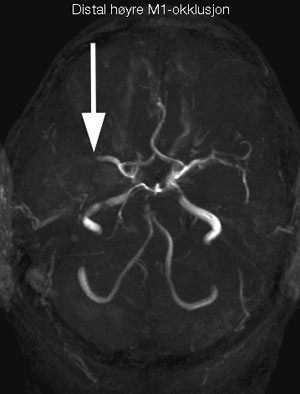

Intraarteriell behandling

Intraarteriell kjemisk trombolyse kan være effektivt ved akutt hjerneinfarkt. Det er imidlertid ikke gjort sammenliknende studier mellom intravenøs og intraarteriell trombolytisk behandling og ingen større studier med intraarteriell trombolytisk behandling versus placebo. Tidsforsinkelsen før man kan starte intraarteriell trombolyse har vært forsøkt kompensert ved kombinert intravenøs og intraarteriell trombolytisk behandling (21, 22). Denne strategien er under videre utprøvning. Intraarteriell trombolyse må foreløpig anses som eksperimentell behandling.

Intraarteriell mekanisk trombolyse (embolektomi) (23) med forskjellige typer instrumenter er beskrevet i små kliniske serier og i en mindre fase 2-studie (MERCI I) (24). Resultatene er lovende og metoden blir utprøvd i større studier. Embolektomi vil også bli utprøvd hos pasienter der intravenøs trombolytisk behandling ikke har gitt rekanalisering (THRUST) i en randomisert studie tilknyttet SITS-trombolyseregisteret. Embolektomi må foreløpig anses som eksperimentell behandling.